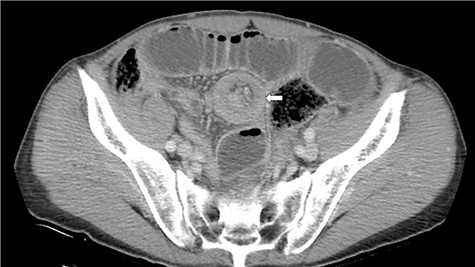

A 72-year-old man was diagnosed with stage IV (cT4N0M0) epithelioid MPM with diffuse invasion of soft tissues of the right chest wall, according to the criteria of International Mesothelioma Interest Group, by computed tomography (CT), positron emission tomography (PET)-CT, and pleural biopsy 18 months ago. He was treated with pemetrexed and cisplatin for 12 months. Because of the appearance of lung metastasis, the patient was treated with nivolumab as second line therapy for 6 months. He complained of vague abdominal pain 2 months ago. He then underwent upper and lower gastrointestinal endoscopy, but no abnormalities were found. He was admitted to our hospital for aggravation of abdominal pain. His abdomen was flat and soft, and he complained of abdominal pain upon applying pressure on the entire abdomen. Hematological tests revealed a raised white blood cell count of 9400/μl and high C-reactive protein level of 10.09 mg/dl. CT scan revealed intussusception of the small intestine (Fig. 1).

CT discloses a typical target sign over the small intestine (arrow).